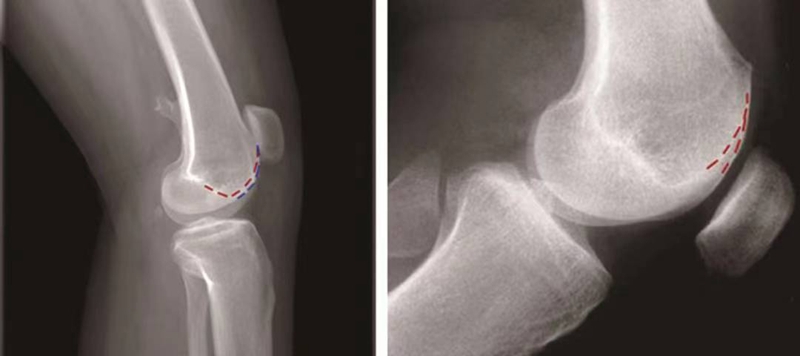

③双轨征(或称为双线征):

是指在膝关节标准侧位像上,代表股骨内外侧滑车的两条线分开,呈双轨样(图13)。它的出现提示股骨内侧滑车发育低平,导致它的前缘出现晚于外侧滑车。

图13 双轨征

(3)股骨滑车发育不良的分型:

1996年,D.Dejour和B.Le Coultre提出了更准确的股骨滑车发育不良的四种分型(图14):

图14 股骨滑车发育异常分型 A型:交叉征;B型:交叉征+突起征;C型:交叉征+双线征;D型:交叉征+突起征+双线征